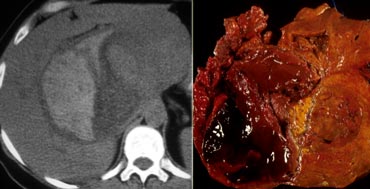

Adenoma with hemorrhage. Adenoma with hemorrhage.

Adenomas may rupture and bleed, causing right upper quadrant pain.

The two most common liver lesions causing hepatic hemorrhage are HA and HCC.

Although adenomas are benign lesions, they can undergo malignant transformation to hepatocellular carcinoma (HCC).

Although malignant transformation is rare, for this reason, surgical resection is advocated in most patients with presumed adenomas.